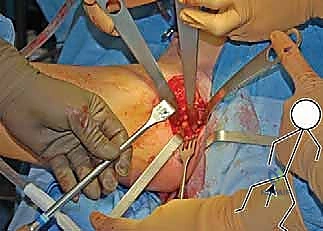

بمجرد اكتمال هذه القطوع الثلاثة، يصبح التجويف الحقي (الكوب) منفصلاً تماماً عن بقية الحوض، مع بقاء إمداداته الدموية سليمة.

4. إعادة التوجيه والتدوير (Rotation & Redirection)

باستخدام أدوات خاصة، يقوم الدكتور هطيف بتدوير التجويف الحقي الحر في ثلاثة أبعاد (للأمام، وللخارج، وللأسفل) حتى يغطي رأس عظم الفخذ بشكل مثالي وميكانيكي سليم. يتم التحقق من الزاوية الجديدة فوراً داخل غرفة العمليات باستخدام جهاز الأشعة السينية المتحرك (C-arm).

5. التثبيت القوي (Fixation)

بمجرد الوصول إلى الوضع المثالي، يتم تثبيت العظام في مكانها الجديد باستخدام براغي معدنية قوية من التيتانيوم أو دبابيس (K-wires). هذا التثبيت يضمن التحام العظام بشكل صحيح خلال فترة التعافي.